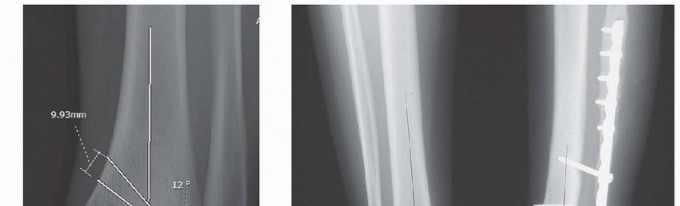

FIG 2 • A. Standing mortise radiograph of the left ankle showing preoperative planning. A 12-degree varus deformity is shown with planning for a 12-degree opening wedge oblique osteotomy with a 10-mm opening at the base. B. Standing AP view of both ankles in a different patient showing preoperative planning, revealing a 17-degree valgus deformity and plans for a 17-degree closing wedge osteotomy. The base of the wedge is planned as 14 mm along the medial tibial cortex.

## The magnitude and plane of the deformity to be addressed should be calculated preoperatively and noted in the preoperative plan (FIG 2A).

## After the deformity is assessed using the methods described by Paley and Tetsworth,4, 5 the position of the center of

## P.561

rotation of angulation (CORA) is identified and a bisector is constructed. Most commonly, this point is very near the physis and articular surface ( FIG 2B).

## Although the osteotomy can be performed at a level consistent with the biology of the bone and allowing for adequate fixation, the correction of the deformity should occur along the bisector.

## The goal of surgical correction should be to obtain an LDTA of about 90 degrees with a tibial mechanical axis that passes through the center of the ankle.